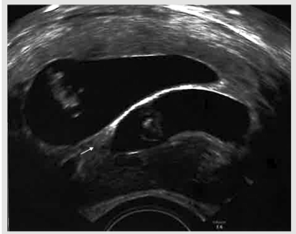

Sau chuyển phôi 15 ngày, nồng độ beta hCG huyết thanh là 2287 mU/mL. Ở tuổi thai 7 tuần, siêu âm ngả âm đạo xác nhận có 2 phôi thai với 2 khoang nguyên bào nuôi tách biệt, dựa trên dấu hiệu lamda của Hiệp hội siêu âm sản phụ khoa thế giới (ISOUG) (hình 2).

Hình 2: Dấu hiệu Lamda trên siêu âm đầu dò âm đạo